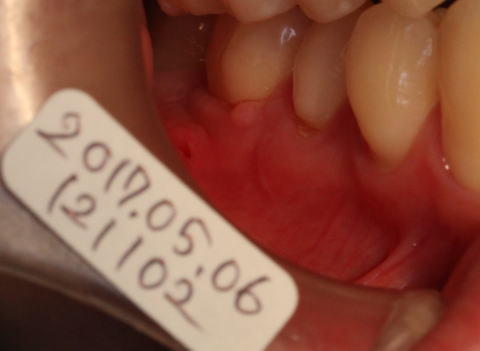

2017-05-06 j術後約2週間後です。 抜糸をしました。 歯ぐきの形はまだいびつです。 |

![]() |